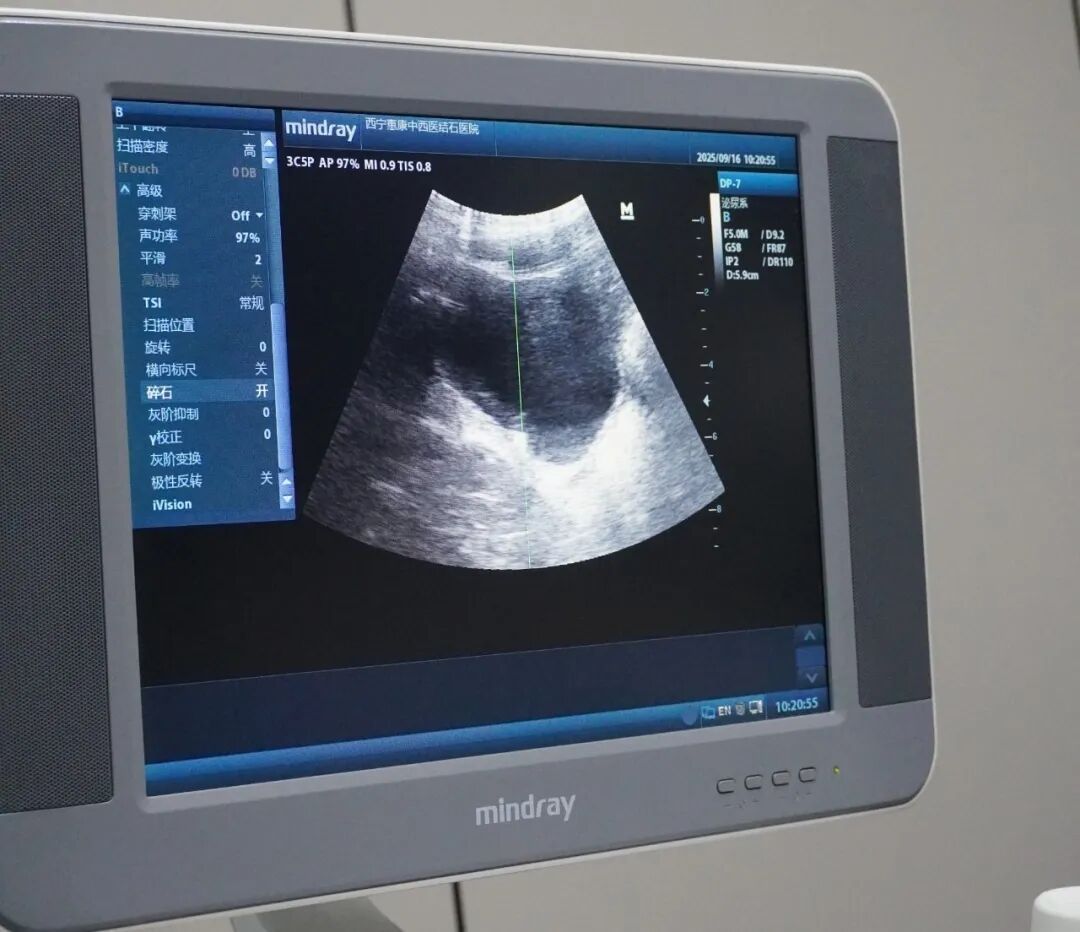

温暖相伴,助力患儿战胜结石病痛 耐心安抚,缓解紧张情绪 小男孩刚来到医院的时候,满脸都是惊恐的神情,毕竟对于一个 6 岁的孩子来说,医院陌生的环境本就容易让人心生畏惧,更何况是要面对那并不了解的结石治疗呢。通过医护人员的耐心引导,患儿顺利完成治疗,术后状态良好。 面对这样小患者,我院的医护团队迅速行动起来。医生用通俗易懂的话语,把复杂的治疗过程拆解开来,让小男孩能够大致明白,这不是什么可怕的 “大怪兽”,而是帮助他把身体里捣乱的 “小石头” 赶出去的办法。 在医护人员的暖心安慰下,小男孩渐渐放下了戒备,那原本挂满泪痕的小脸也逐渐有了一丝放松的神情。看着医护们亲切又真诚的模样,小男孩终于鼓起了勇气,决定积极配合治疗。 治疗过程中,医护团队严格按照操作规范执行,通过实时监测设备参数,确保治疗方案的安全性与合理性,尽可能降低患儿的不适感。 十几分钟的时间,在大家的共同关注下悄然过去,而这场体外碎石治疗也顺利结束了。结束后的小男孩,仿佛一下子就摆脱了之前病痛带来的阴霾,又恢复了往日的活泼,那纯真的笑容再次绽放在他的脸上,也让在场的每一位医护人员都由衷地感到欣慰。 这虽然只是我院日常诊疗中的一个小小片段,但却体现了医护人员的专业素养与人文关怀。对于每一位前来就医的患者,无论年龄大小,我们都始终秉持着用心关怀、用爱治疗的理念,努力让患者在就医过程中感受到温暖与安心。我们深知,身体上的病痛已经给患者带来了痛苦,那我们就更要在心理上给予他们足够的慰藉,用专业的医疗技术和体贴的人文关怀,帮助他们战胜疾病,重新拥抱健康的生活。 未来,我院也将继续坚守这份初心,持续开展技术培训与服务改进,为更多的患者带去希望与健康,持续优化医疗服务质量。